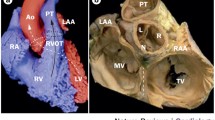

Normally, the RVOT lies anterior to the LVOT as it courses superiorly and leftward to connect to the pulmonary artery. The LVOT is located posteriorly and courses rightward to connect to the aortic root. The pulmonic valve is superior, anterior, and leftward to the aortic valve. The aortic root is centrally located and in direct contact with both atria, the interatrial septum, the mitral valve, and the posterior RVOT (Fig. 1) [20]. It has been well described that myocardial sleeves can extend above the pulmonic and aortic valves into the great vessels, and may be the source of arrhythmias [21]. In nearly three-fourths of patients, sleeves of myocardium extend above the pulmonic valve into the pulmonary artery [22]. Myocardial sleeves similarly extend above the aortic valve into the aortic root in over one-half of patients, most commonly in the right (55 %) and left (24 %) coronary cusps, rarely in the noncoronary cusp (<1 %).

Anatomy of the ventricular outflow tracts and relationship to electrocardiogram morphology. The free wall of the RVOT lies anteriorly within the chest, just beneath the sternum and precordial ECG leads. The electrocardiographic forces generated by ventricular tachycardia from the free wall of the RVOT are negative through much of the precordium, as the activation wavefront moves away from the anterior chest wall. As one progresses posteriorly toward the spine, from the septal RVOT to the right coronary cusp, left coronary cusp, aortomitral continuity, and superior mitral annulus, the activation wavefront moves increasingly toward the precordial leads, generating a greater degree of positivity in lead V1 as well as an earlier precordial transition. We divide the RVOT into sites 1 (most rightward), 2, and 3 (most leftward). Site 1 of the RVOT generates a positive complex in limb lead I, as the wavefront moves toward the left arm. By site 3 of the RVOT, the wavefront moves away from the left arm, generating a negative complex in lead I. RVOT right ventricular outflow tract, RCC right coronary cusp, LCC left coronary cusp, NCC noncoronary cusp, AMC aortomitral continuity.

As the outflow tracts are superiorly located, positivity in the inferior ECG leads (II, III, and aVF) is the rule. The RVOT free wall is situated most anteriorly within the chest (Fig. 1), just beneath the sternum and precordial ECG leads. As one progresses posteriorly, the septal RVOT is encountered next, followed by the right coronary cusp, left coronary cusp, aortomitral continuity, and superior mitral annulus. The RVOT free wall is therefore the most negative in the precordium, with a left bundle configuration in lead V1 and precordial transition at V4 or later. As one moves posteriorly toward the spine, greater degrees of positivity are observed in lead V1 and the precordium transitions earlier. The precordial transition is typically V3 or V4 for the septal RVOT, V2 or V3 for the right coronary cusp, V2 or right bundle configuration in lead V1 for the left coronary cusp, qR configuration in lead V1 for the aortomitral continuity and positivity throughout the precordium for VT originating from the superior mitral annulus.

The borders of the RVOT are the pulmonic valve (superiorly), tricuspid valve (inferiorly), interventricular septum (medially), and RV free wall (laterally). The majority (>80 %) of RVOT tachycardias originate along the septum, just beneath the pulmonic valve [27]. We divide the RVOT into free wall and septal aspects, and describe the most rightward extent as site 1 (positive in lead I, Fig. 1 and Table 1), the middle as site 2 (biphasic or isoelectric in lead I), and the most leftward extent as site 3 (negative in lead I). Beneath sites 1, 2, and 3 are sites 4, 5, and 6 [28]. VT originating from the RVOT free wall has notching in the inferior leads and a later precordial transition than VT originating from the septal RVOT.